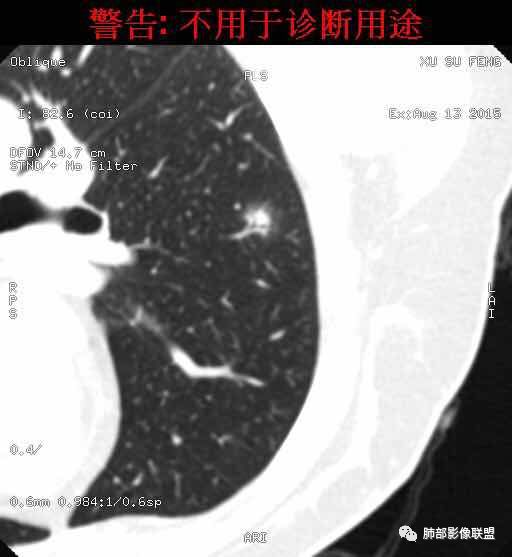

我怎么感觉支气管是通的,周围的晕又比较软,我考虑炎性病变,隐球菌可能大(如下图)

南边:首先自然是看GGO的边界如何?清楚吗?哞:边界模糊南边:其次内部的支气管如何?Coke with ice:清。可见穿行。哞:有通过,也有阻塞吧M-Imaging :进入一半南边:常规的窗宽窗位边界好像不清

也有点散南边:我觉得支气管走形自然,远端稍扩张M-Imaging :略有扩张南边:倾向于炎性宇宙星空:支持M-Imaging :腺癌的GGO,非常清晰的结果:

1.隐球菌病灶往往是实性密度结节为主伴周边边界不清楚的晕,有时可见晕内细软毛刺。

2.隐球菌病灶形态往往圆钝柔和,缺乏收缩能力,很少出现腺癌的那种胸膜牵拉和棘状突起。

3.病灶内支气管安然无恙隐球菌病灶更加多见